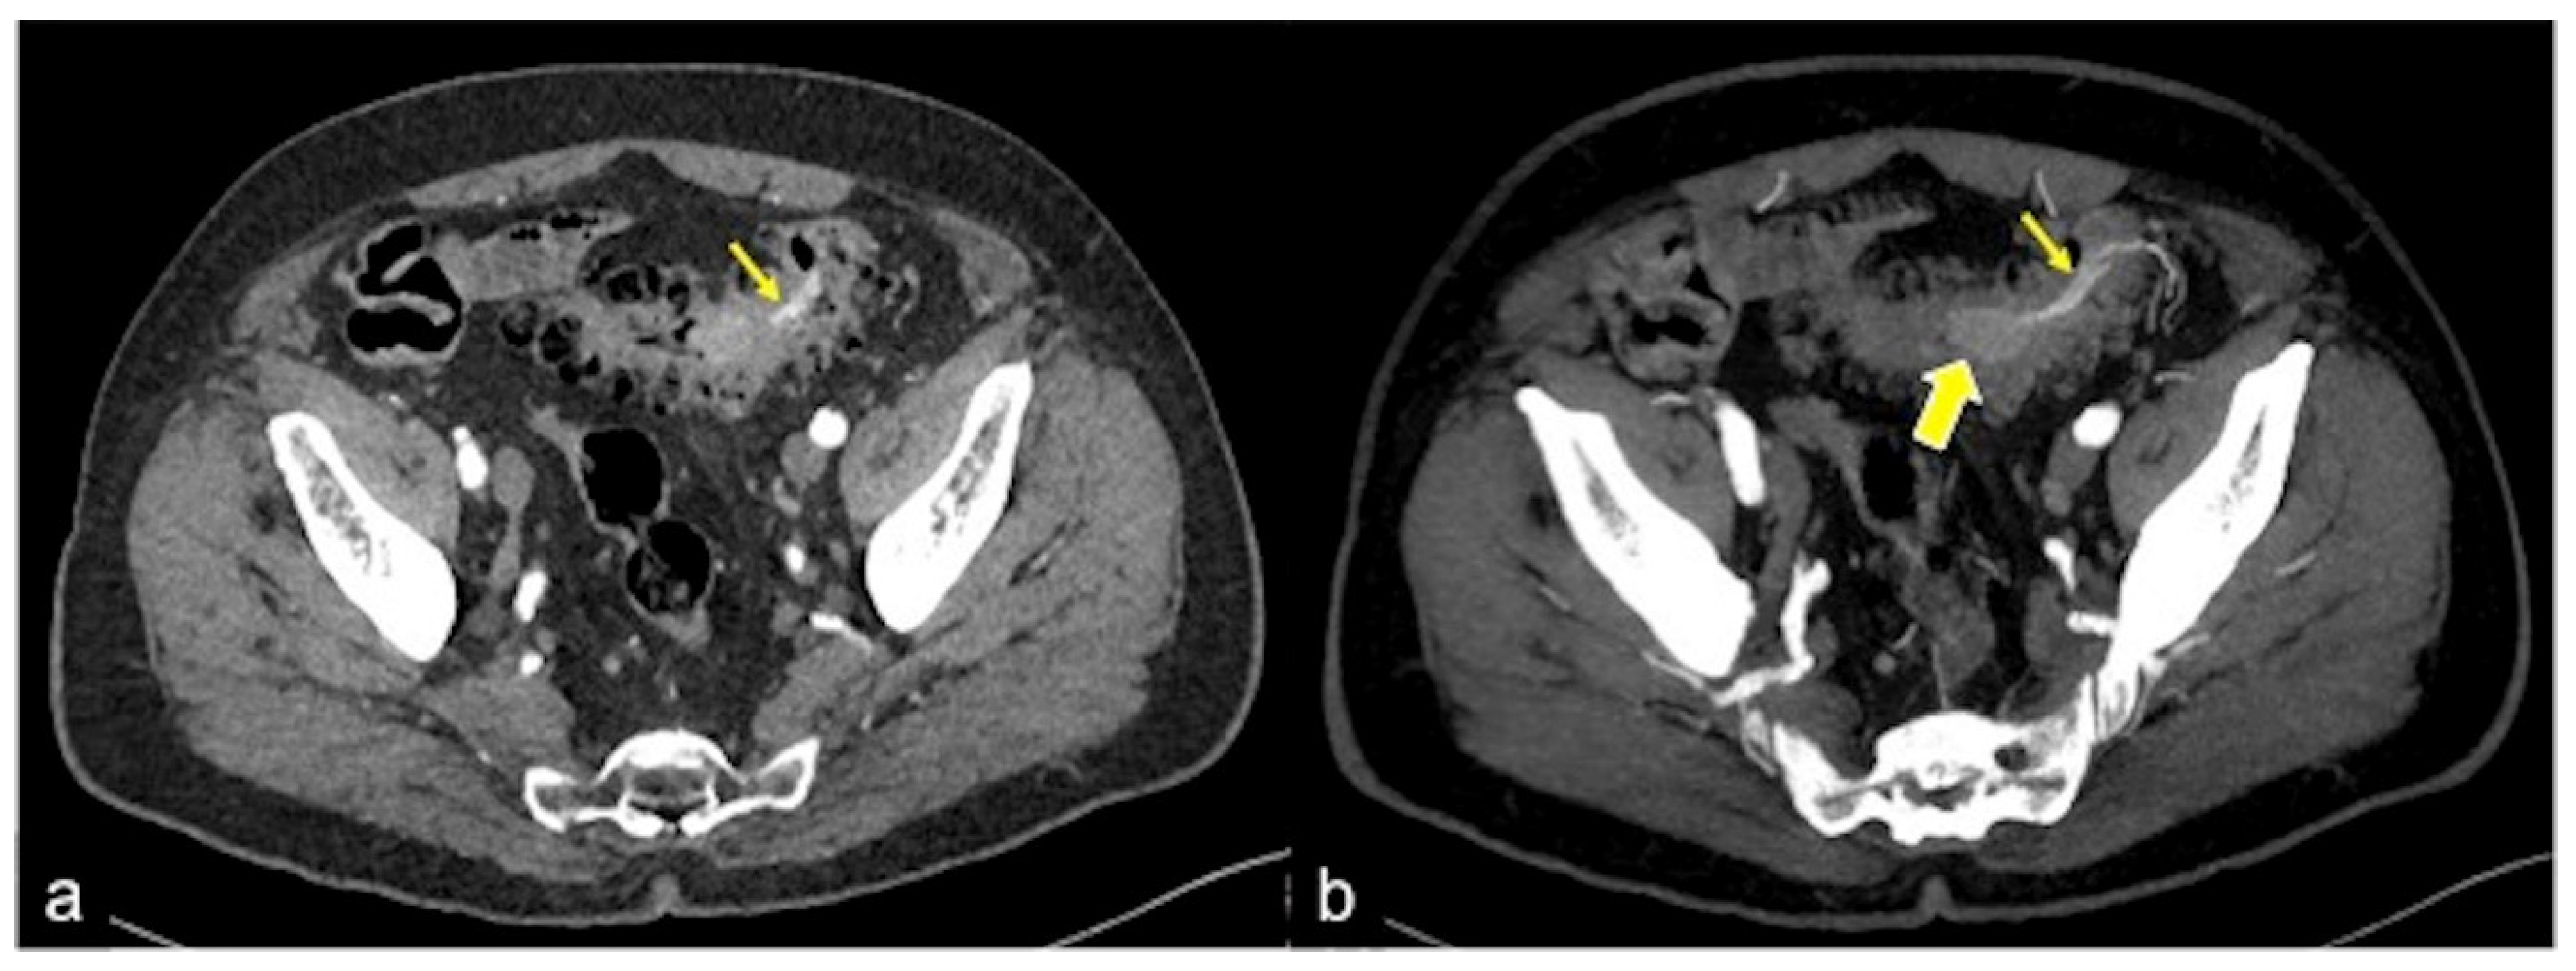

| Diverticulosis (Figure 33) | Asymptomatic or bleeding. | Protruding sacs where the vessels pass through the muscularis layer, between the mesenteric and antimesenteric taenia. |

| Angiodysplasia (Figure 5 and Figure 34) | Asymptomatic or bleeding. | Small hyperdense nodules within the intestinal wall, best defined in the portal phase of the study. |

| Colorectal Cancer/Polyps (Figure 6, Figure 36, Figure 37 and Figure 38) | Bowel obstruction with or without bleeding. | Adenocarcinoma: irregular wall thickening with or without stenosis [25]; Polyps: mass-forming protrusions in the intestinal lumen with vascularised peduncle. |

| Inflammatory Bowel Disease (Figure 39 and Figure 40) | Haematochezia-rectorrhagia. | Acute: thickening of the walls, engorgement of the adjacent vasa recta, hyperaemia of the mucosa and infiltration of perirectal fat. Chronic: the colon and rectum are narrowed and shortened, without haustra, and with proliferation of the perirectal fat. |